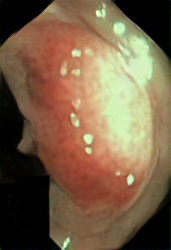

A few sample images and the corresponding masks of the polyp dataset in HyperKvasir are shown in Fig 2. The polyp images are RGB images. The masks of the polyp images are single-channel images with white () for true pixels, which represent polyp regions, and black () for false pixels, which represent clean colon or background regions. In this dataset, there are different sizes of polyps. The distribution of polyp sizes as a percentage of the full image size is presented in the histogram plot in Fig 3, and we can observe that there are more relatively small polyps compared to larger polyps. Additionally, a subset of this dataset was used to prove that the performance of segmentation models trained with small datasets can be improved using our SinGAN-Seg pipeline, and the whole dataset was used to show the effect of using SinGAN-Seg generated synthetic images instead of a large dataset which has enough data to train segmentation models. In this regard, this dataset was used for two purposes:

After training SinGAN-Seg models, we generated random samples per real image using the input scale , which is the lowest scale that uses a random noise input instead of a re-scaled input image. For more details about these scaling numbers and corresponding output behaviors, please refer to the vanilla SinGAN paper [56]. Three randomly selected training images and the corresponding first synthetic images generated using scale are depicted in Fig 4. The first column of the figure represents the real images and the ground truth mask annotated from experts. The rest of the columns represent randomly generated synthetic images and the corresponding generated mask.